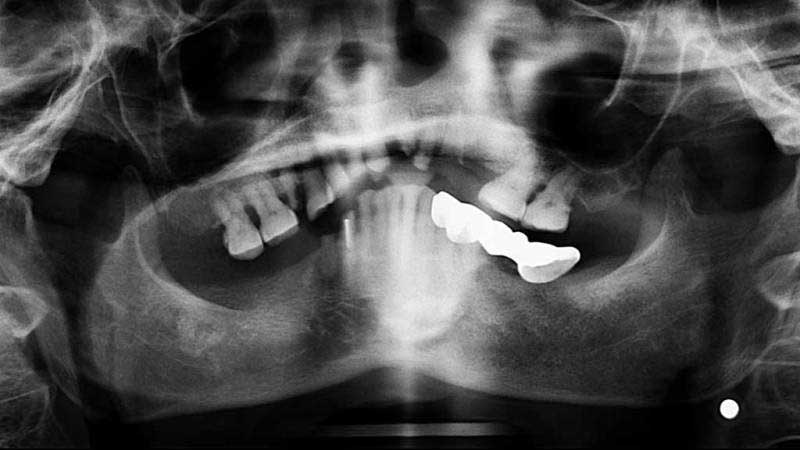

案例3